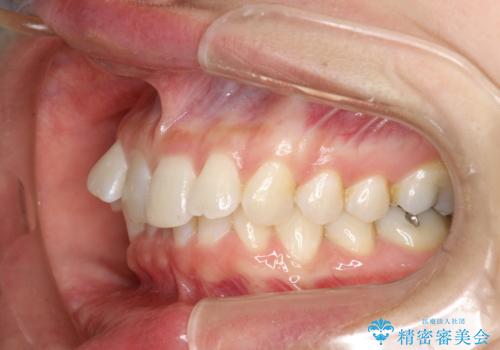

- 前歯のがたつきを気にされて来院されました。

右上の前から2番目の歯が前方に大きく傾いており、下の前歯もガタガタしていました。

インビザラインにて、歯と歯のあいだをわずかに削り並べる計画としました。

しっかりとマウスピースを使用していただけたので、順調に治療を終えることができました